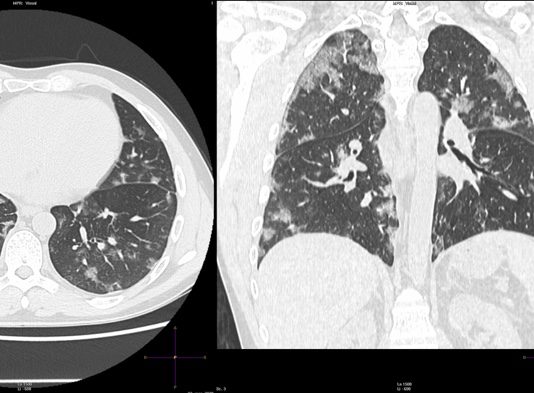

Uomo 57 anni, nessuna comorbidità nota.

Febbre e tosse non produttiva.

Leucocitosi. Insufficienza respiratoria ipossemica e ipocapnica.

Sospetto contatto con soggetti zona rossa. Tampone positivo NCOV 19.

HRTC Torace